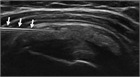

1. 急性の石灰沈着性滑液包炎は、腱板内に沈着した石灰が肩峰下滑液包へ流出して発生する結晶性滑液包炎である。突然発症する例が多い。

1. 腱板内に沈着した石灰が大きくなり、慢性化してインピンジメント症状や関節拘縮を引き起こすこともある。

1. 無症候性の石灰沈着症の発生率は人口の2.7~20%で、30~50歳に好発する。有症状の沈着症は50歳前後であり、女性(男女比は3:2)と棘上筋腱に多い。